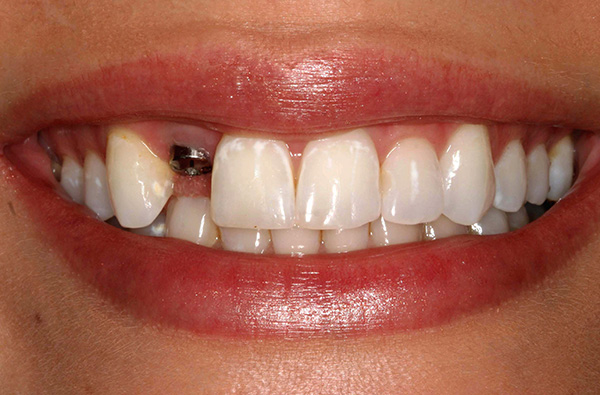

A foto abaixo mostra os implantes removidos da mandíbula: